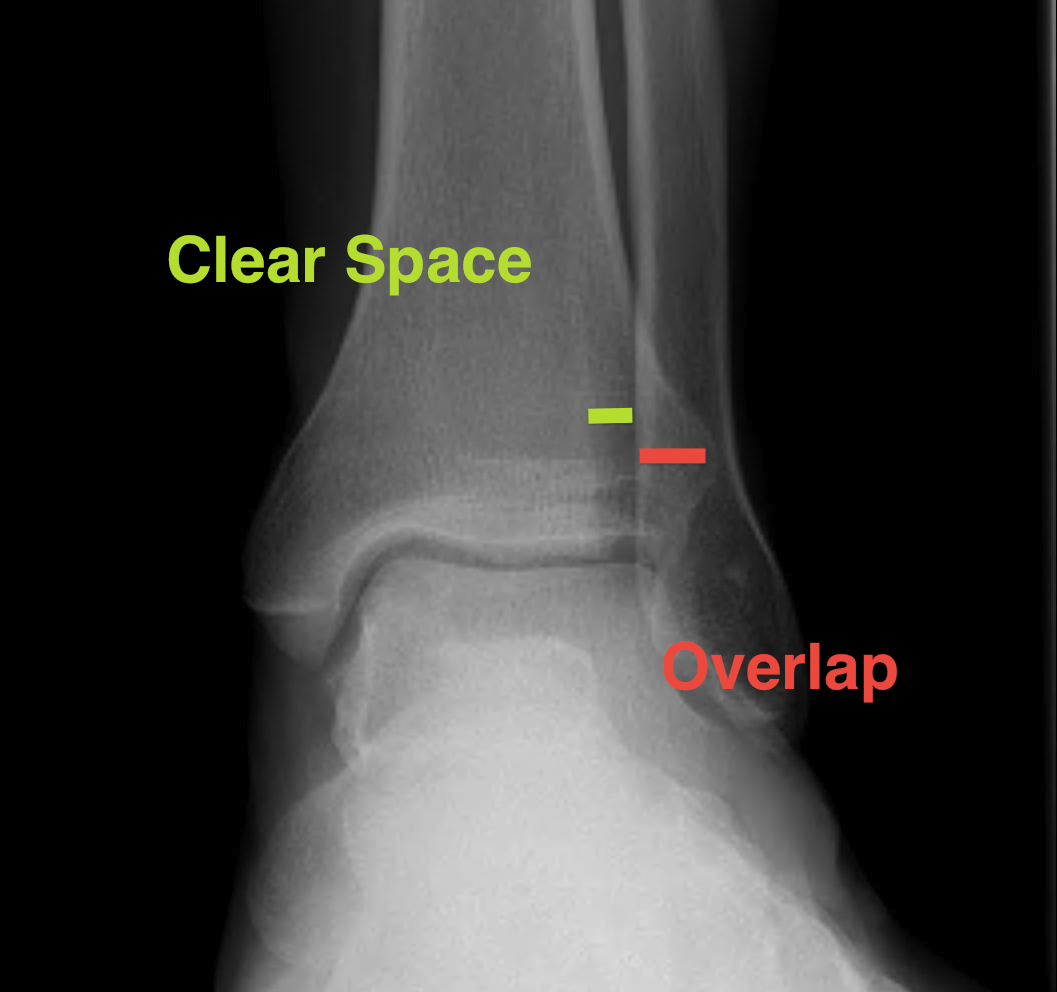

Increased tibio-fibular clear space  Overlap Increased medial clear space

Medial border of the fibula

Lateral border of the posterior tibia (incisura fibularis)

Measured 1 cm above the plafond

Overlap of the fibula and the anterior tibial tubercle

Medial talus to lateral medial malleolus

<5mm AP and mortise

> 6 mm AP view

> 1 mm mortise view

< 4mm

Equal to superior clear space

Syndesmotic injury Syndesmotic injury

Deltoid ligament injury

Lateral talar shift

Ankle AP Xray Syndesmotic Measurements Ankle Mortice Xray Syndesmotic Measurements Mortise

Lateral talar shift / increased medial clear space / deltoid ligament injury

Ankle Fracture Increased Medial Clear SpaceAnkle Fracture Increased Medial Clear Space 2Maisonnerve

Tibia / fibular overlap < 1mm / syndesmotic injury

Ankle Fracture Syndesmosis WidenedAnkle Diastasis